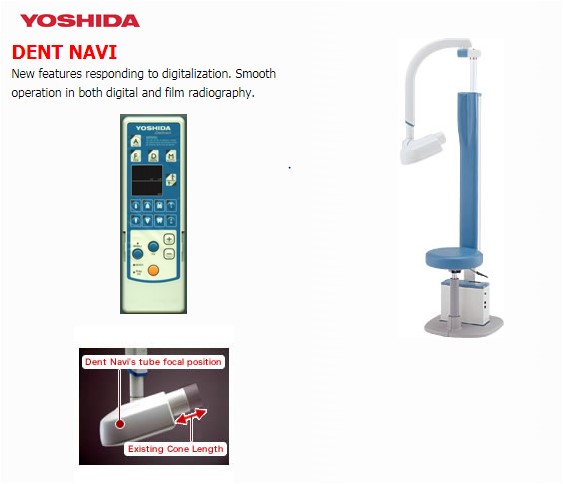

Ngoài ra, việc sử dụng máy X-Quang cho ra hình ảnh nhanh chóng giúp phát hiện các nguy cơ răng miệng tiềm tàng như: hội chứng rối loạn thái dương hàm, u nang vùng miệng, bệnh nha chu, khối u/ung thư miệng, nhiễm trùng,… Thêm vào đó, việc đầu tư những thiết bị chẩn đoán hình ảnh hiện đại (như hệ thống Dent Navi của Yoshida) có thể giúp Bác Sĩ và bệnh nhân giảm tiếp xúc với bức xạ (tia X) đến 40% lượng bức xạ so với chụp bằng máy X-quang truyền thống.

Hiện nay, trên thị trường có nhiều dòng máy chụp phim X-quang nha khoa nhưng để đảm bảo hình ảnh sắc nét, độ an toàn cao và tính ứng dụng tối ưu. Nhiều phòng khám đã tin tưởng lựa chọn Dent Navi của Yoshida (Nhật Bản). Đây là dòng máy X-quang kỹ thuật số tiên tiến được N.K.Luck phân phối chính hãng.

Hiện tại trên thị trường thiết bị Nha Khoa Việt Nam có rất nhiều loại máy chẩn đoán hình ảnh đang được sử dụng các Phòng Khám. Trong đó, dòng máy chẩn đoán hình ảnh Dent Navi của Yoshida, Nhật Bản (N.K.Luck phân phối chính hãng) đang là sản phẩm được tin dùng nhất hiện nay.

Chụp X-quang kỹ thuật số làm giảm lượng tia và các hình ảnh bị mờ do bệnh nhân chuyển động khi chụp

Yoshida – một trong những thương hiệu cung cấp thiết bị Nha Khoa lâu đời tại Nhật Bản (hơn 100 năm), nhà sản xuất dòng máy chẩn đoán hình ảnh nổi tiếng Dent Navi (X-quang DC trong miệng).

- Thiết bị này cho hình ảnh rõ nét nhờ vào phương pháp chỉnh lưu dòng điện một chiều cao tần, phát ra ít tia X nên an toàn cho người sử dụng hơn.

- Thời gian chụp chỉ 0.01s cho hình ảnh sắc nét, giảm tình trạng ảnh mờ do bệnh nhân chuyển động.

- Vị trí cố định trên sàn, giảm rung lắc (có vị trí gắn ốc cố định nếu sàn nhà nhấp nhô)

- Thiết kế thông minh giúp thiết bị định vị chính xác hơn các góc cạnh hơn những loại máy khác.

- Cài đặt thời gian chụp cho thiết bị một cách tự động, chỉ cần một thao tác đơn giản là nhấn nút để bắt đầu chụp.

- Chuyển đổi dễ dàng điện áp đầu tube giữa 70kV sang 60kV – từ chế độ chụp người lớn sang trẻ em.

- Tương thích với cả người châu Á và châu Âu, ghế ngồi được nâng lên hoặc hạ xuống nhanh chóng, dễ dàng.